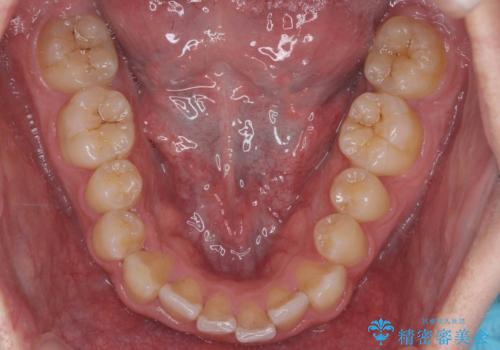

- 前歯のすきまと八重歯を主訴に来院。

左上の乳犬歯が残っており、その下から生えてくるはずの犬歯(永久歯)が左上小臼歯部に萌出していました。

左上の乳犬歯は根もしっかりしていたため、

➀そのまま矯正する。乳歯がいずれダメになったときにそこはブリッジかインプラントを検討する

②乳歯は抜歯し、ブリッジかインプラントを矯正後に入れる

を提案し、➀を選択されました。

将来的にインプラントは希望されないとのことだったため、乳歯の部分は隙間を開けてインプラントを入れる用のすき間を確保するということは特に行いませんでした。

乳歯をそのまま並べたため、上顎の左右の犬歯の幅は非対称になっています。